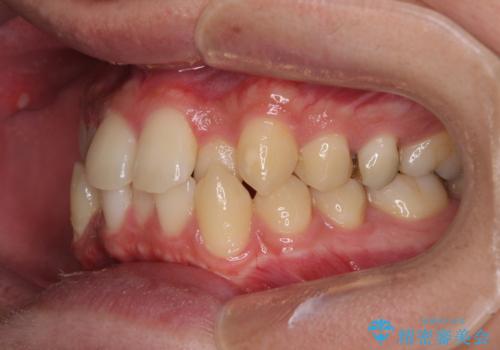

前歯のクロスバイト インビザラインによる矯正治療

- 上下のクロスバイトと前歯のデコボコを気にして来院された患者様です。

インビザラインを用い、IPR(歯と歯の間を削る)と歯列全体を拡大させることで、歯並びを整えていくこととしました。